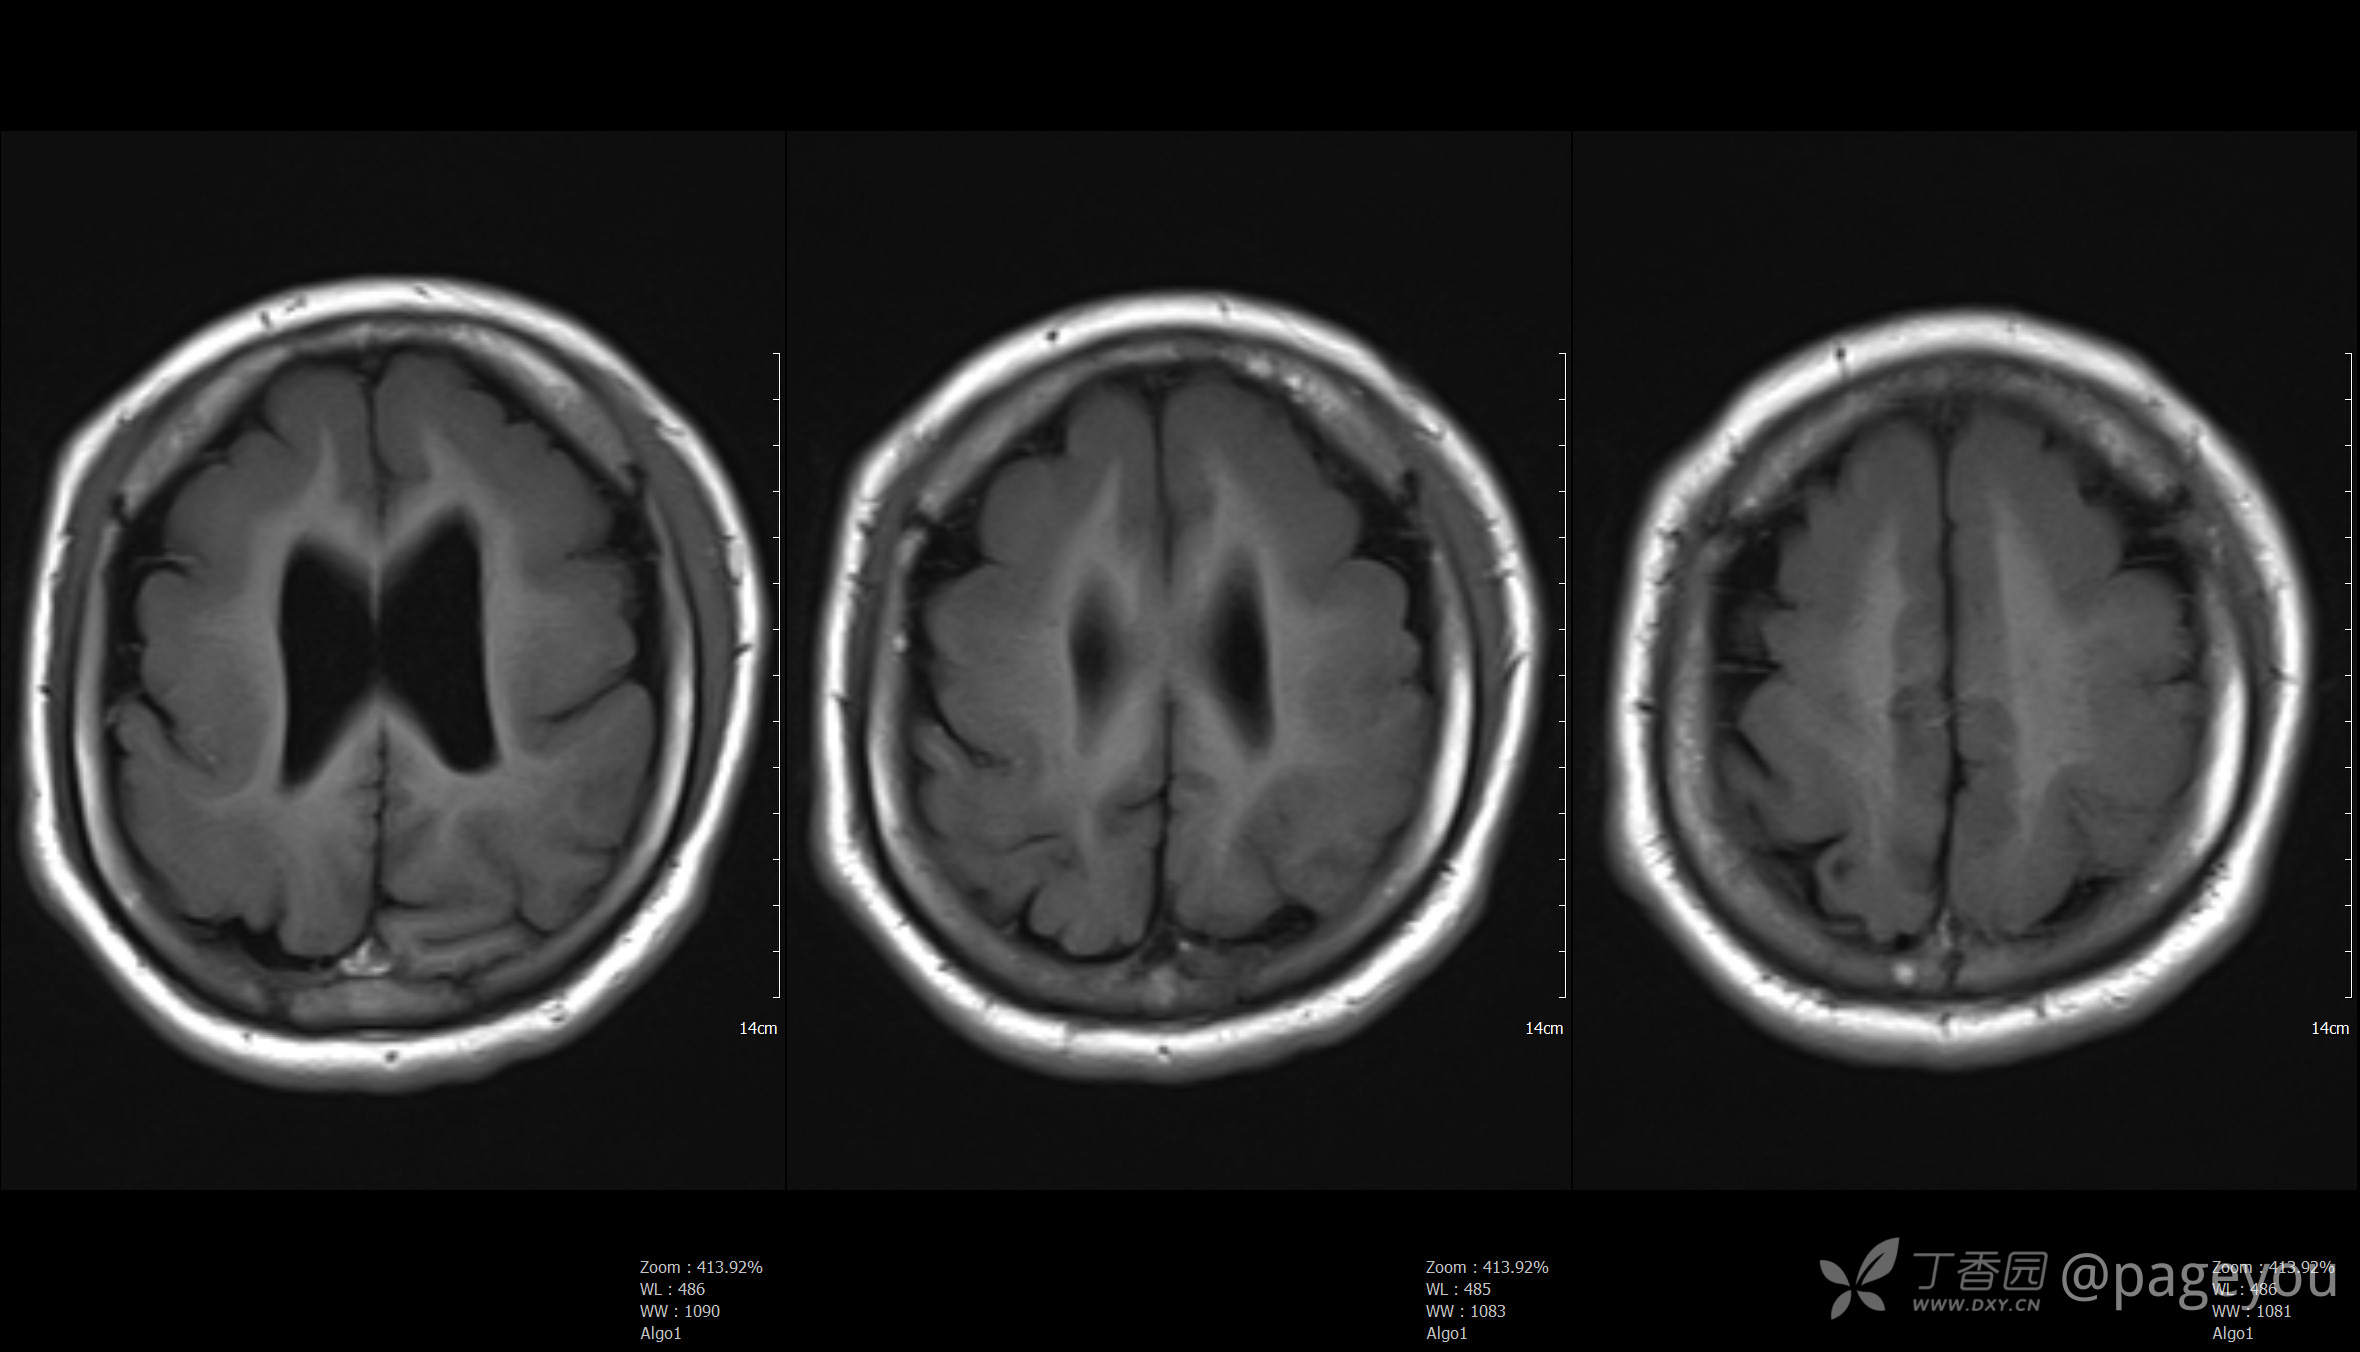

头颅MRI: